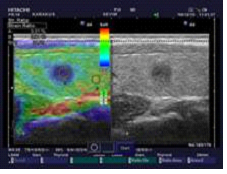

Radioactive iodine therapy (RAI) is a treatment method used to in cases of Graves’ disease(GD), toxic multinodular guatr and solitary toxic nodu¨le and residual tissue after thyroidectomy or in the treatment of metastases capable of capturing iodine. The biological basis of the treatment is the inhibition of follicle cell functions. Side effects such as thyroid swelling, radiation thyroiditis and sialadenitis are rare. Radiation thyroiditis tends to occur within two weeks after RAI administration and is generally asymptomatic in most patients. Approximately % 1-5 of patients with GD develop radiation thyroiditis after RAI treatment. Radiation causes ınflammation that develops as a result of exposure of a large residual tissue to a high radiation dose may cause tenderness in the thyroid tissue or neck, erythema and edema, pain when swallowing, rarely airway obstruction, and in some patients, a thyrotoxic state. Symptoms generally begin 1- 10 days after treatment. Pain and tenderness in the thyroid and neck area are mild and disappear within 3-7 days. There may be a temporary hyperthyroidism attack at this time. Mild symptoms are usually relieved with non-steroidal antiinflammatory drugs. In more severe cases, corticosteroid treatment (30 mg/day prednisone) provides rapid relief of symptoms. In case of thyroid storm, symptoms can be controlled with corticosteroids, if severe adrenergic symptoms are accompanied by beta blockers and if necessary antithyroid drugs. Here we will present a case of radiation tyroditis developing after Graves Diseaes(GD). A 71- year-old patient with a diagnosis of Graves’ disease was treated with 20 mcı radioactive iodine due to elevated liver function tests under antithyroid drug therapy. 1 week after radioactive iodine treatment, she was admitted to our outpatient clinic with complaints of pain in the throat and difficulty swallowing. Thyrotoxicosis was detected in the tests. Oral cavity looked natural and sensivity was detected in the neck area. No respiratory distress was detected. Newyl developed tracheal stenosis was detected on the cervical graphy. Color doppler pattern 3 and edema in the thyroid gland was detected on the ultrasonography. The patient ‘s complaıns were primarily evaluated as thyroiditis secondary to radıoactive iodine treatment. The patient was started on oral methylprednisolone sodıum succinate, non-steroidal anti-inflamatory and betablocker treatment. The patient’s complaints regressed under treatment. In conclusion, radiation thyroiditis is a complication of RAI for the treatment of GD and may cause morbidity. Radiation thyroiditis should be suspected as the etiology of patients presenting with neck pain and difficulty swallowing immediately after RAI